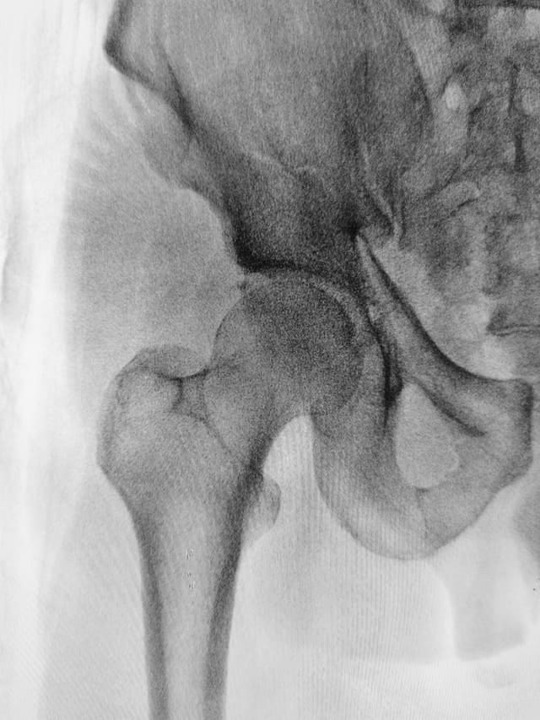

関節の過可動性: 関節が通常よりも極端に動くことが一般的で、関節の脱臼や亜脱臼を引き起こす可能性があります。

関節の固定: 関節の重度の脱臼や亜脱臼がある場合、外科手術が必要になることがあります。